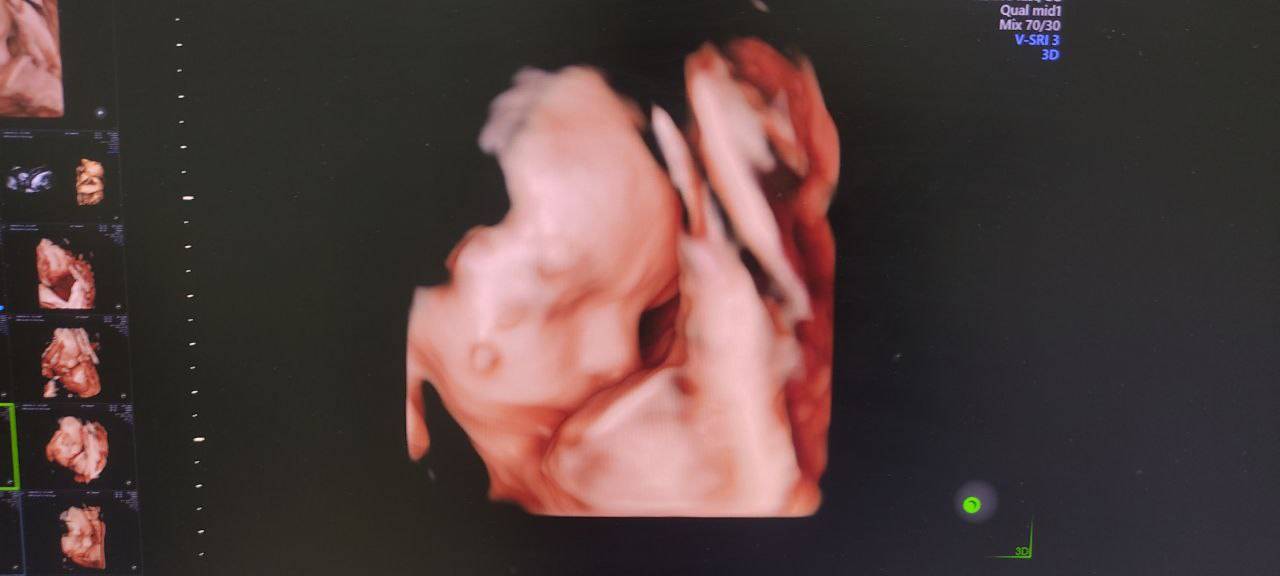

Второй скрининг при беременности: малыш опережает срок

Сходили сегодня посмотреть на нашу бусинку. А наша бусинка, уже бусина. Со второго скрининга начала опережать акушерский срок на неделю.

Долго и упорно ловили ее, но дала посмотреть на свой профиль и то ближе к концу. Но спасибо и за это